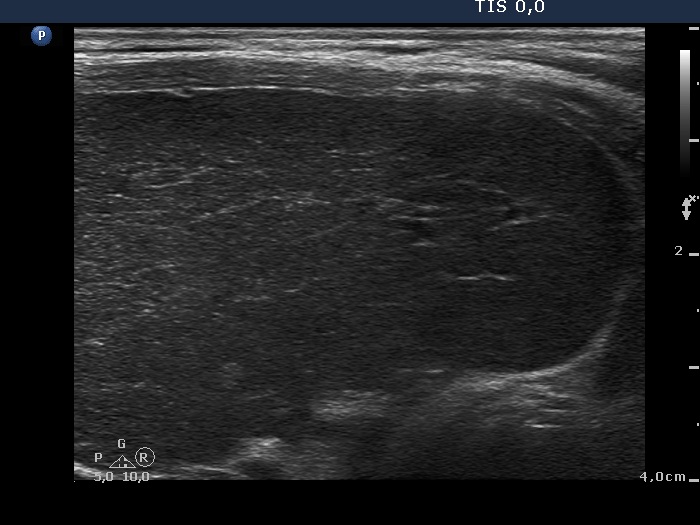

Consecutively operated patients with autoimmune thyroid disease - case 26 (1674) (ultrasonographic picture 7)

Lower part of the left lobe, longitudinal view.